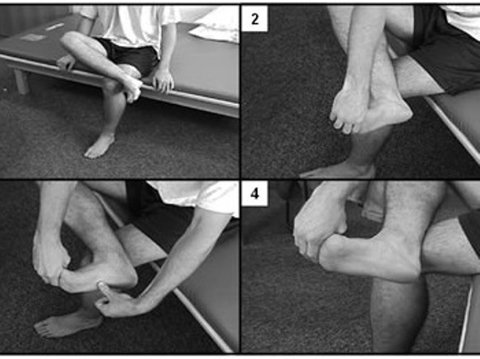

ب)کشش عضلات کف پا

1-پنجه پا را با دست گرفته و به سمت مچ پا کشش می دهیم.